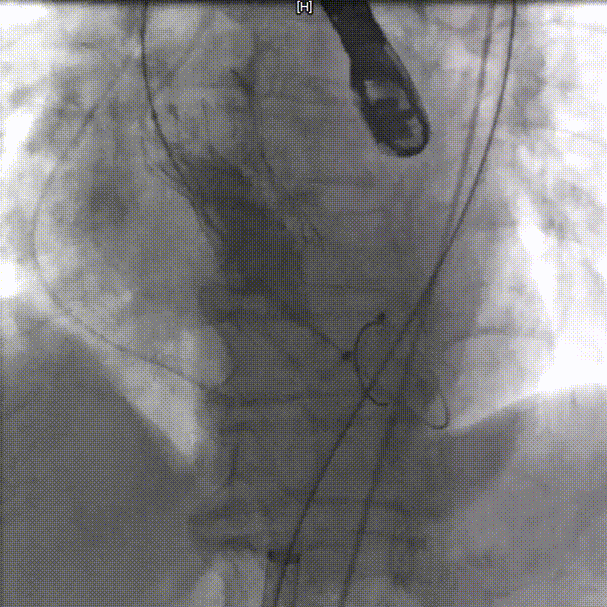

右侧主入路造影

左侧辅入路造影

主动脉根部造影

18mm球囊预扩,冠脉灌注良好

输送器过弓

瓣下3mm定位

左冠窦侧偏深,需回收再定位

回收调整至零位定位,释放到工作位位置合适

完全释放后无反流,冠脉灌注良好

超声看位置合适,无反流

降主动脉良好

外周入路良好

患者压差从64mmHg降为4mmHg,效果显著。